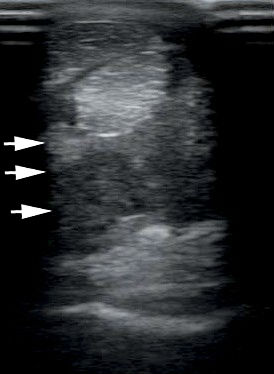

A betegséget ultrahanggal diagnosztizáljuk. Fontos, hogy a sérülés kialakulása után legalább két hetet várjunk a végleges diagnózis felállításával, mert gyakori, hogy az ultrahangos kép még tovább romlik ez alatt az idő alatt, és a túl korán végzett ultrahangozással alábecsülhetjük a sérülés mértékét.

Az első képen egy súlyosan sérült, teljesen felbomlott szerkezetű járulékos szalagot mutatnak a nyilak. A második képen III. jelzi az egészséges párját.